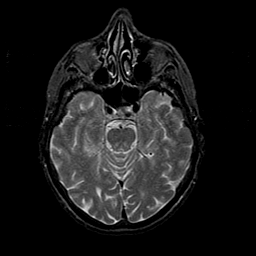

Normal aging, overlay -- Slice #19